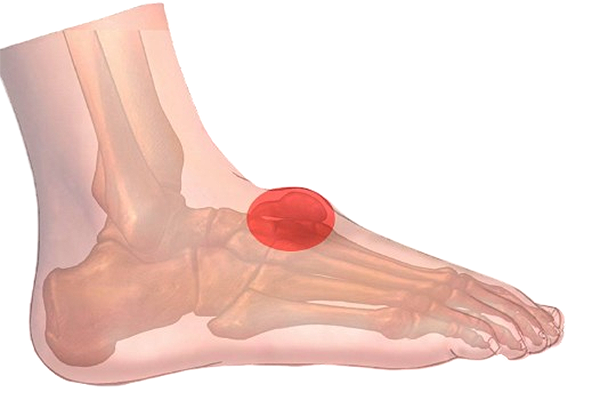

Bultos en los pies: Qué es un quiste sinovial

¿Has notado recientemente un bulto en los pies y no sabes a qué se debe? La aparición de bultos en los pies en muchos casos